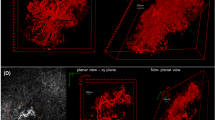

Volume-rendering three-dimensional image analysis of macular neovascularization in age-related macular degeneration

Eye (2024)